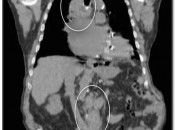

CT Portion of the Exam:  Its value lies in its excellent anatomic detail, as demonstrated in the case above.  In this patient presenting for post-treatment assessment of lymphoma, the CT clearly demonstrates abnormal soft tissue density above and below the diaphragm.  From the CT scan, we know abnormal soft tissue exists, its size and precisely where it is located. What we do not know from the CT scan is the answer to the ultimate clinical question: Does this remaining soft tissue represent active malignancy or post-therapeutic scarring — Does this patient still have cancer? For the answer, we must turn to the PET portion of the examination.